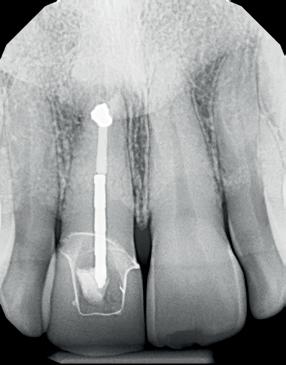

Op basis van de eerste indruk die ik krijg tijdens het globale klinische onderzoek, wordt een orthopantamogram (zie OPT bij intake) gemaakt. Samen met de meegestuurde röntgenopnames (zie solo’s) wordt eenvoudig vastgesteld dat er sprake is van ernstig botverlies, bijvoorbeeld bij de 16, 17 en de 18 tot 100% verlies aan alveolair bot. De 16 vertoont daarnaast een grote peri-apicale laesie. In het eerste kwadrant lijkt daarom alleen de 12 een goede prognose te hebben. De 12 vormt samen met de 16 een vierdelige brug en deze constructie lijkt dus verloren. Overigens vermoed ik dat de 12 eigenlijk een cuspidaat is en ontbreekt de 12 (agenesie). Daarnaast worden sterk verdiepte ontstoken pockets geconstateerd bij de 16, 17 tot 12 mm en zijn de elementen sterk verhoogd mobiel. De 11 lijkt als enige element van de gehele dentitie niet te zijn behandeld.

4. Pre-chirurgische OPG.